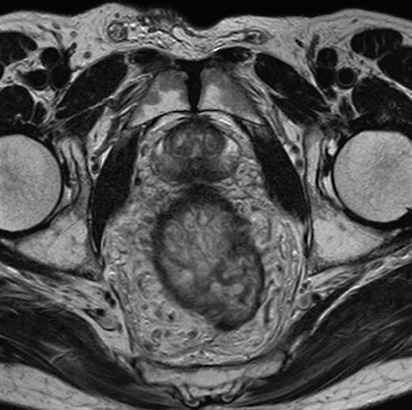

La RMN es el procedimiento preferido para diagnosticar un gran número de posibles problemas o condiciones anormales en diferentes partes del cuerpo. En general, la RMN crea imágenes que puedan mostrar diferencias entre tejidos sanos y no sanos.

Los médicos usan la RMN para examinar el cerebro, la columna vertebral, las articulaciones (ej.: rodilla, hombro, cadera, muñeca y tobillo), el abdomen, la región pélvica, los senos, los vasos sanguíneos, el corazón y otras partes del cuerpo.

Estos exámenes de rutina son:

· Pelvis (óseo, útero y ovarios, próstatas)